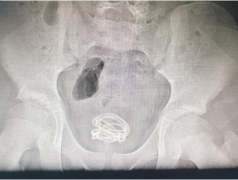

创业三年后,博迈医疗的首个心血管介入产品完成了研发和海外注册,进入国际市场接受挑战。在之后短短的5年时间里,博迈医疗已研发推出了十多个系列产品,涵盖了心血管介入、外周血管介入和血管通路等多个领域;拥有多项发明专利和全球独家创新产品。这些高端医疗器械,已远销包括欧美日等医疗发达国家和地区在内的50多个国家和地区,在多个国家已实现了两位数级的市场占有率,打破了国际巨头的优势技术壁垒和国际市场垄断。